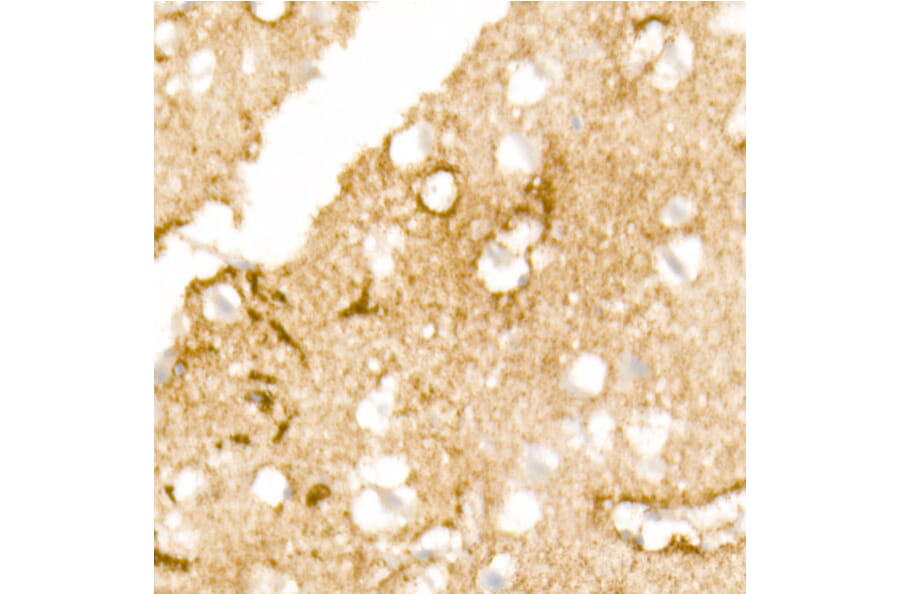

Immunohistochemistry analysis of paraffin-embedded human brain tissue using Anti-Aquaporin 4 Antibody [ARC54345] (A80530) at a dilution of 1:200 (40x lens). Perform high pressure antigen retrieval with 10 mM citrate buffer pH 6.0 before commencing with IHC staining protocol.

Immunohistochemistry analysis of paraffin-embedded mouse brain using Anti-Aquaporin 4 Antibody [ARC54345] (A80530) at a dilution of 1:200 (40x lens). Perform high pressure antigen retrieval with 10 mM citrate buffer pH 6.0 before commencing with IHC staining protocol.